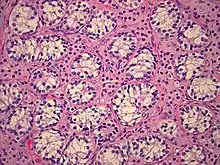

The gonads in individuals with PAIS are testes, regardless of phenotype;[2] during the embryonic stage of development, testes form in an androgen-independent process that occurs due to the influence of the SRY gene on the Y chromosome.[27][28] Cryptorchidism is common,[1][2] and carries with it a 50% risk of germ cell malignancy.[29] If the testes are located intrascrotally, there may still be significant risk of germ cell malignancy; studies have not yet been published to assess this risk.[29]